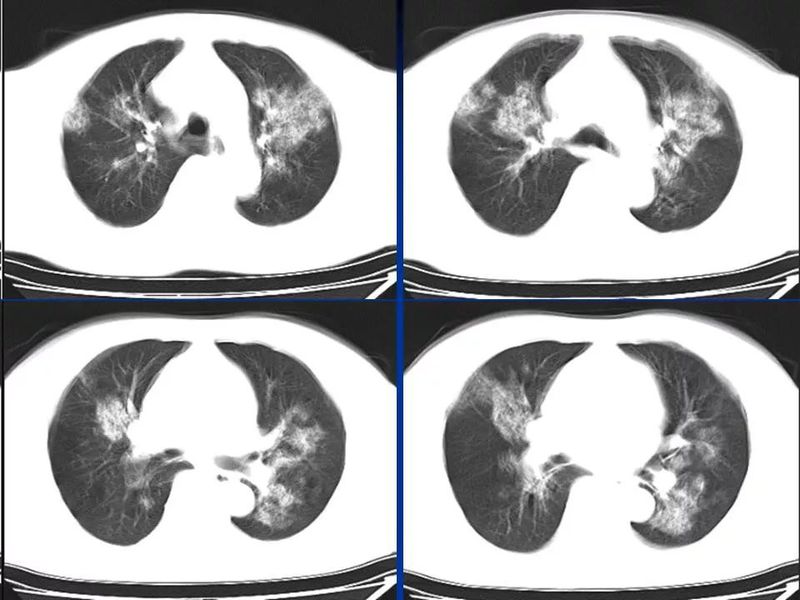

主任提醒:这个病很容易误诊为肺炎!